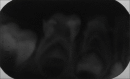

Dental anomalies of number and forms may occur in the primary and permanent dentition. Various terms have been used to describe dental twinning anomalies: Germination, fusion, concrescence, double teeth, conjoined teeth, twinned teeth, geminifusion, and vicinifusion. Fused tooth is a developmental anomaly that is seen more frequently in the primary than the permanent dentition. Double tooth involving deciduous anterior teeth is found mostly in the mandible. Very few cases of nonsyndromic double primary molar have been reported in the literature. The succeeding permanent tooth is often found missing congenitally in the same region. This article reports a very rare unilateral occurrence of an anomalous, primary mandibular first macromolar formed by fusion with a dysmorphic premolar like supernumerary tooth in deciduous dentition period. Instead of agenesis of succedaneous tooth, the double tooth has been succeeded by normally developing mandibular first premolar in the same region.